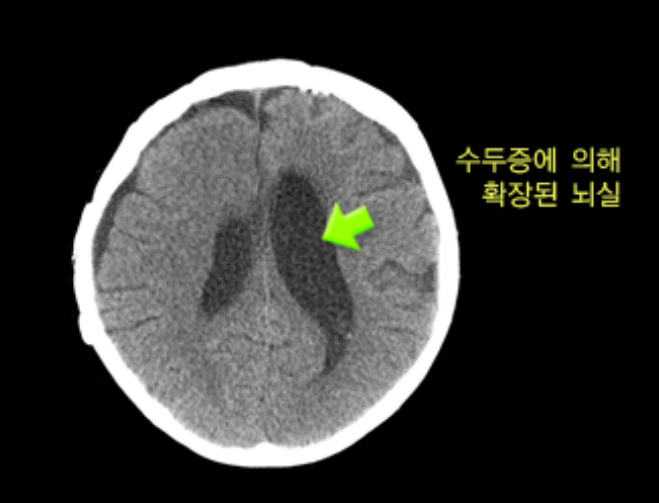

- 수두증: 뇌실 내 뇌척수액이 축적되어 발생하는 질환으로, 보행 장애, 요실금, 치매 증상이 나타납니다. 수술을 통해 치료가 가능합니다.